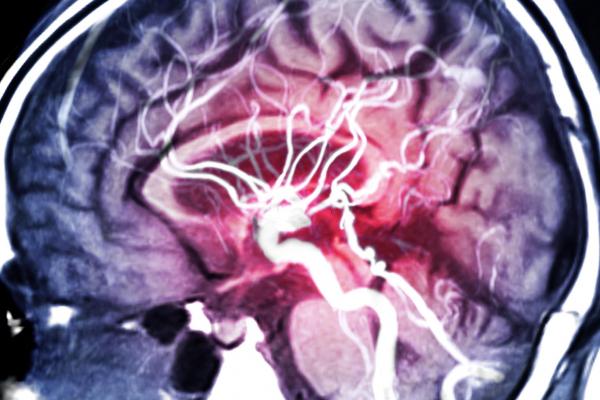

La capacidad de nuestro cerebro y su funcionamiento sigue siendo un misterio para los investigadores en el tema, por ello resulta necesario que más profesionales se encarguen de su estudio y muestren interés en desvelarlos. Emagister se alegra en ofrecerte en esta ocasión la gran oportunidad de tener un postgrado experto en neurología, gracias al programa diseñado e impartido por la Escuela de Postgrado de Psicología y Psiquiatría. El mismo se imparte bajo una modalidad a distancia y con una duración totalmente flexible para tu mayor comodidad al momento de estudiar. Culminada tu formación, el centro te otorgará tu correspondiente titulación.

Durante la presente formación, te adentras en profundidad en las variantes y características de las diferentes áreas cerebrales, así como los sistemas que comparten sus funciones. Por ello, inicialmente te introduces en la estructura anatómica y fisiológica del área neuronal, explorando la valoración de las funciones y procesos neurológicos y conociendo las manifestaciones que se presentan en las alteraciones de estas. Al tener claro esta base, puedes introducirte en las distintas patologías y alteraciones que afectan al cerebro.